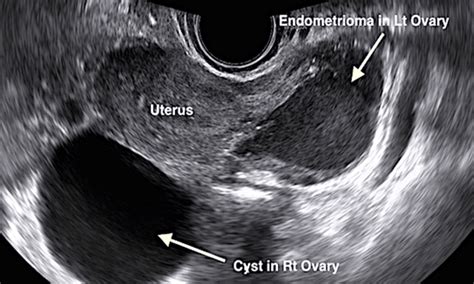

- Endometriomas: Linked to endometriosis, they may start small but cause significant inflammation and twisted ovaries.

Imaging Advances Improve Detection

Modern ultrasound technology, including transvaginal ultrasound and 3D imaging, enhances the ability to spot small, concerning cysts early. MRI and CT scans further clarify suspicious lesions, reducing misdiagnosis and enabling timely treatment.